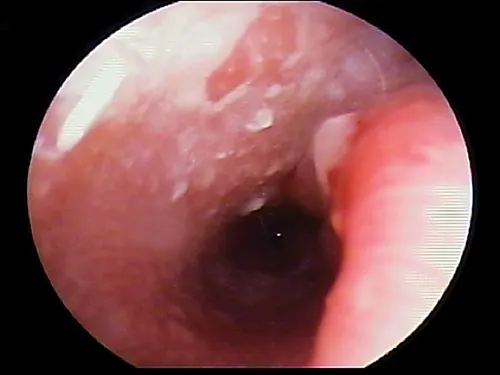

Ulceration

Ulceration of the ear canal epithelium is most often associated with a severe, chronic bacterial otitis externa (often Pseudomonas spp). The bacteria releases cytopathic enzymes resulting in ulceration (Figure 6). Tumors within the ear canal may be present and should be noted (Figure 7).

selected slide image

FIGURE 6

1 / 5

Ulceration of the ear canal. Note the disruption of the surface epithelium.